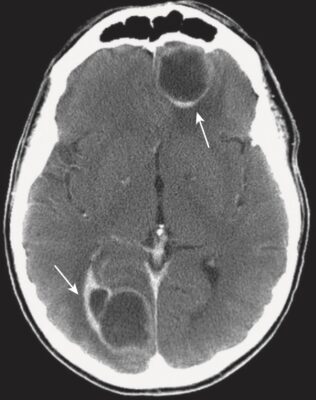

Đột quỵ do xuất huyết (Hemorrhagic Stroke)

- Trong phần lớn các trường hợp, có tăng huyết áp kèm theo. Khoảng 60% trường hợp xuất huyết do tăng huyết áp xảy ra ở hạch nền. Các vùng khác thường liên quan là đồi thị, cầu não và tiểu não (Hình 18).

- Nhận biết xuất huyết trong não (nói chung):

- Máu tươi mới thoát mạch hematocrit bình thường có thể nhìn thấy như là tăng tín hiệu trên phim chụp CT não không cản quang ngay sau biến cố (xem Hình 18). Điều này được cho là do protein trong máu (chủ yếu là hemoglobin).

- Phân tán máu vào hệ thống não thất có thể xảy ra trong chảy máu não do tăng huyết áp (xem Hình 11).

- Khi cục máu đông bắt đầu hình thành, máu trở nên đậm hơn trong khoảng 3 ngày do cục máu đông bị mất nước.

- Sau ngày thứ 3, cục máu đông giảm đậm độ và không nhìn thấy được trong vài tuần tiếp theo. Cục máu đông giảm đậm độ từ bên ngoài vào trong do đó nó có vẻ như co rút lại.

- Sau khoảng 2 tháng, có thể chỉ còn lại một vùng nhỏ giảm đậm độ (Hình 19; Box 1).